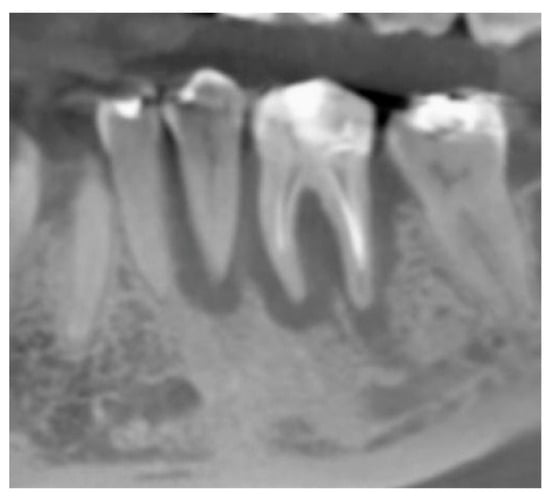

The vertical average defect was 9.16 mm, buccal lateral/palatal 7.0 mm, and mesio-distal 10.3 mm. The measurements were intraoperatively performed with a millimeter periodontal probe. The endodontic material mechanically cleaned before the tooth was placed inside the Tooth Transformer device. The endodontic material was removed using a drill bur with the attention to cut the canal in excess with the aim to remove all the cement. No surgical complications were registered. Pre and post-operative X-rays (section from CBCT) were collected from the same case (Figure 1, Figure 2, Figure 3 and Figure 4). After four months, 13 histological and histomorphometrical evaluations were performed (Figure 5). The Bone Volume/Total Volume average (BV%) was 41.47 (S.D. ± 11.51), the Residual Graft/Total Volume average (Graft%) was 16.60 (S.D. ± 7.09), and the Vital Bone/Total Bone average (VB%) was 21.89 (S.D. ± 9.72). No extraneous material (gutta-percha or cement) was detected in all samples (Table 3).

Figure 1. X-ray, elements 35 and 36 surrounded by a big bone defect.